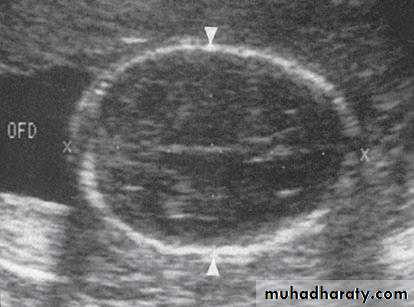

The crown-rump length (CRL)the head circumference (HC) from 14 to 20 weeks gestation.

The biparietal diameter (BPD)

It is more accurate than prediction from the last menstrual period(LMP),even if the woman is certain of her datesIn the latter part of pregnancy, measuring fetal abdominal circumference (AC) and HC will allow assessment of the size and growth of the fetus and will assist in the diagnosis and management of fetal growth restriction. In addition to AC and HC,BPD and FL, when combined in an equation, provide a more accurate estimate of fetal weight (EFW) than any of the parameters taken singly